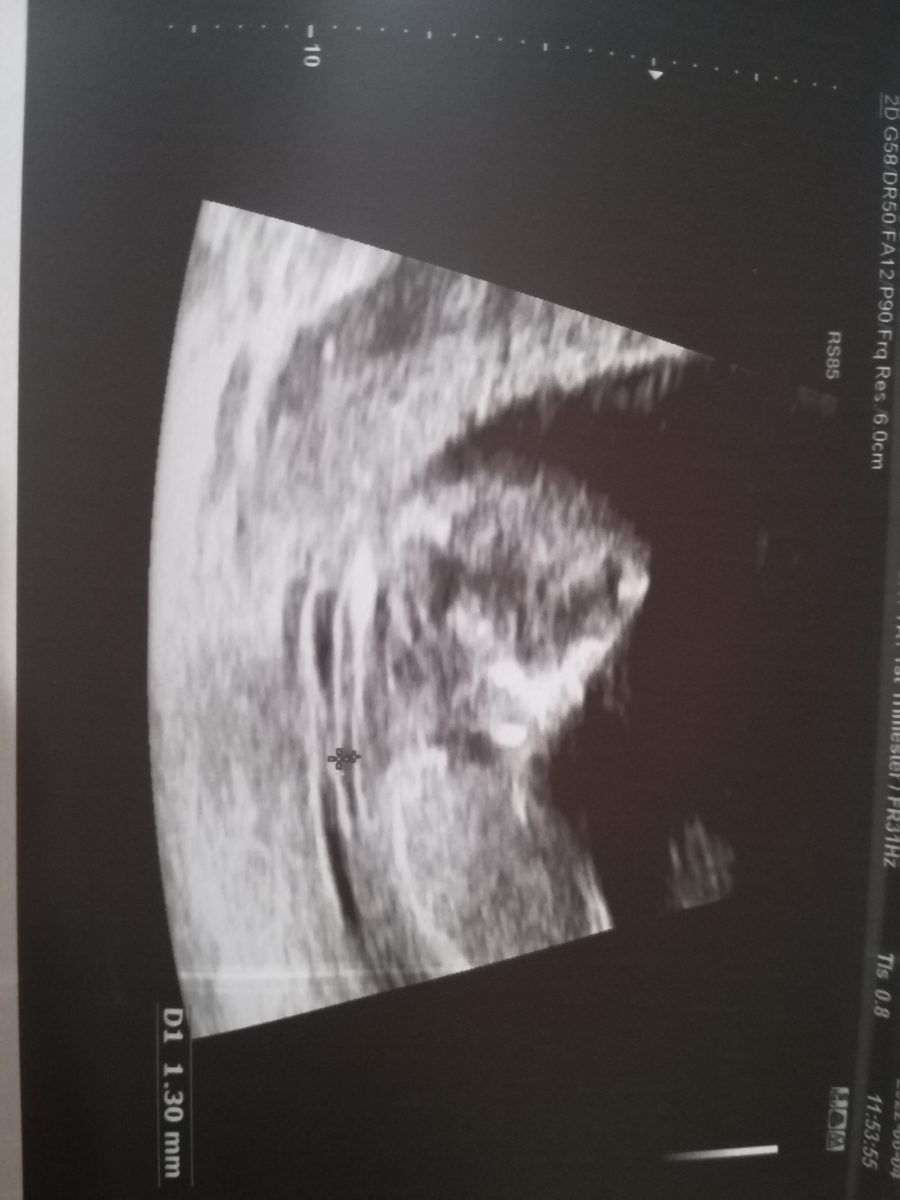

سونو NT انجام دادم میشه برا منم حدس بزنید نی نی چیه؟ دکترم احتمال داد بعدش میگم

از روی این عکس احتمال زیاد دختره چون سرش گرده

ولی تو بقیه عکس ها پسر چون سرش حالت مربعی شکل داره

من از یه دکتری پرسیدم گفت جنین دختر سرش گرده و پیشونی هم همینطور

ولی جنین پسر سرش مربعی شکله